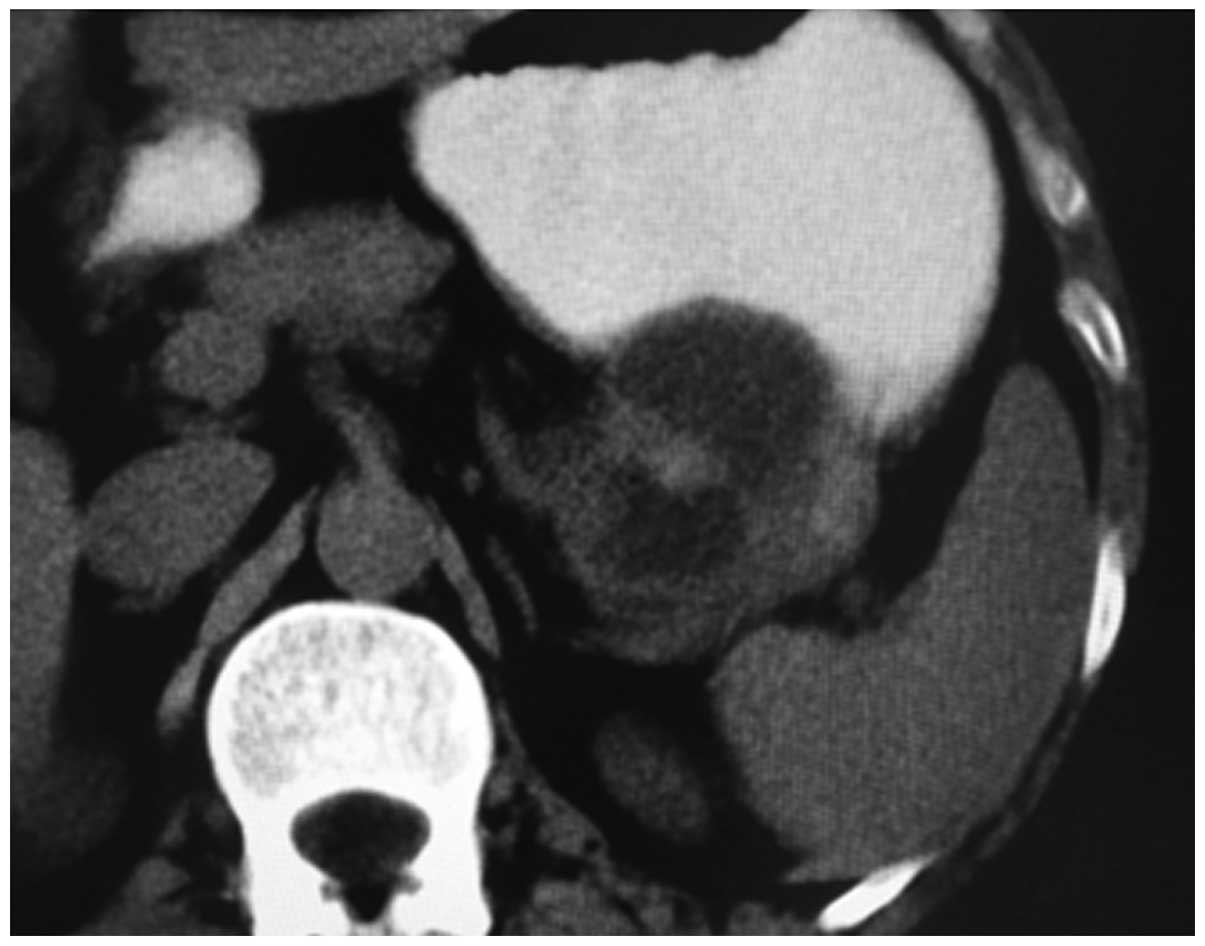

A 48-year-old male presented with a five-month history of epigastralgia, with weight loss of ∼3 kg in one month. One month prior to hospitalization, a gastroscopy revealed an ulcer in the duodenal bulb and chronic superficial gastritis. The patient did not respond to anti-ulcer therapy. There was no remarkable past medical history with no alcohol consumption or history of smoking. In addition, the patient’s family medical history was unremarkable. A physical examination revealed epigastric tenderness upon palpation, however, no palpable abdominal masses were identified. Laboratory examinations reported the following results: Red blood cell (RBC) count, 4.75×1012 cells/l; hemoglobin (HB), 144 g/l; white blood cell (WBC) count, 7.3×109 cells/l; albumin (ALB), 43.9 g/l; total bilirubin (TBIL), 19.9 μmol/l; direct bilirubin (DBIL), 2.8 μmol/l; aspartate aminotransferase (AST), 30 U/l; and alanine aminotransferase (ALT), 13 U/l. The carbohydrate antigen (CA)19-9, CA50, α-fetoprotein (AFP) and carcinoembryonic antigen (CEA) levels were 134 U/ml, 50 U/ml, 49 ng/ml and 12 ng/ml, respectively. Abdominal ultrasonography revealed an ∼8×5 cm cystic mass in the tail of the pancreas. Computed tomography revealed a large complex cystic and solid mass in the tail of pancreas (Fig. 1).